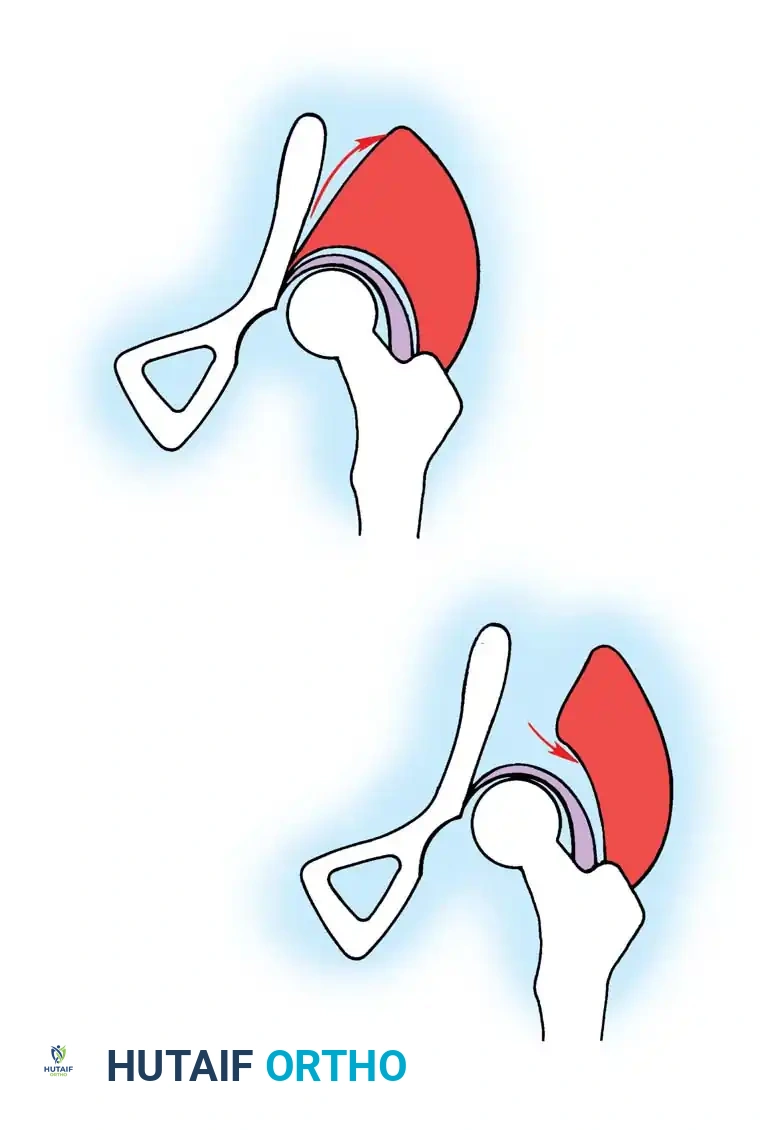

- Biomechanics: A complete transverse cut is made through the ilium just above the acetabulum to the sciatic notch. The entire acetabulum is rotated anteriorly and laterally, hinging on the pubic symphysis.

- Fixation: A triangular bone graft (harvested from the iliac crest) is placed in the osteotomy site, and the construct is stabilized with threaded Kirschner wires.

Diagrammatic representation of the Salter Innominate Osteotomy. Note the complete iliac cut and the placement of the triangular bone graft to redirect the acetabulum.

- Pemberton Pericapsular Osteotomy:

- Indications: Severe dysplasia with a capacious acetabulum.

- Biomechanics: An incomplete cut is made through the ilium, curving down to the triradiate cartilage, which acts as a hinge. This reshapes the acetabular roof, reducing its volume and improving anterolateral coverage.